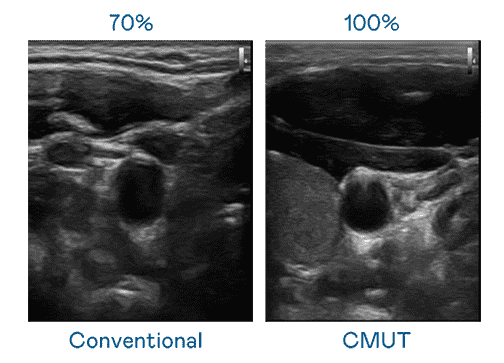

CMUT 技术是一种用电容式微机电元件来产生超音波讯号的技术。。。。与传统 PZT 压电式技术相比,,,CMUT 频宽增加 30%,,,,更宽频的超音波讯号让影像解析度大幅提升,,,是实现高影像品质医疗超音波扫描、、促进精准医疗发展的关键技术。。

超音波影像的解析度高低,,,,首先取决于探头能发出的讯号频宽。。。。优游UB8 CMUT 可提供高清晰的超音波讯号,,,,提供高频宽、、、高灵敏度、、、、影像纹理细节更高的超音波影像,,,,协助医护人员缩短影像判读时间及利用精准的医疗影像进行诊断。。。